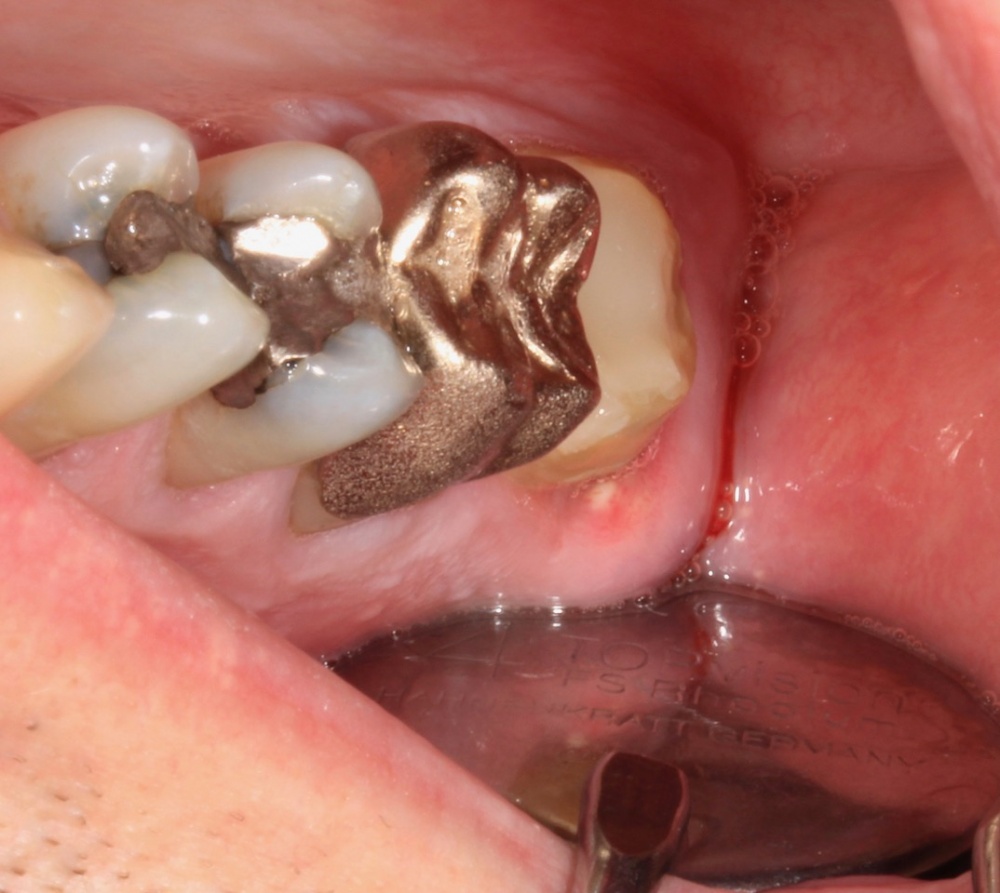

Nach ausführlicher Aufklärung der vorhandenen Therapiealternativen entschied sich der Patient für die Revisionsbehandlung. Diagnostisch wichtig war in diesem Fall die Bestimmung des inserierten Wurzelstiftes. Röntgenologisch unterscheiden sich Glasfaser- und Metallstifte aufgrund der physikalischen Eigenschaften des Materials deutlich, sodass es sich hier zweifelsfrei um einen Metallstift handelte. Durch das röntgenologisch sichtbare Gewinde ließ sich die Art des Stiftes bestimmen. So war nach Entfernen der Krone das vorsichtige Freischleifen des Stiftkopfes (Abb. 6) wichtig, um den Stift mit einem speziellen Schlüssel ausdrehen zu können (Abb. 7).

Damit ließ sich eine laterale Belastung des Stiftes und der Wurzel durch ungewolltes Hebeln weitestgehend vermeiden.